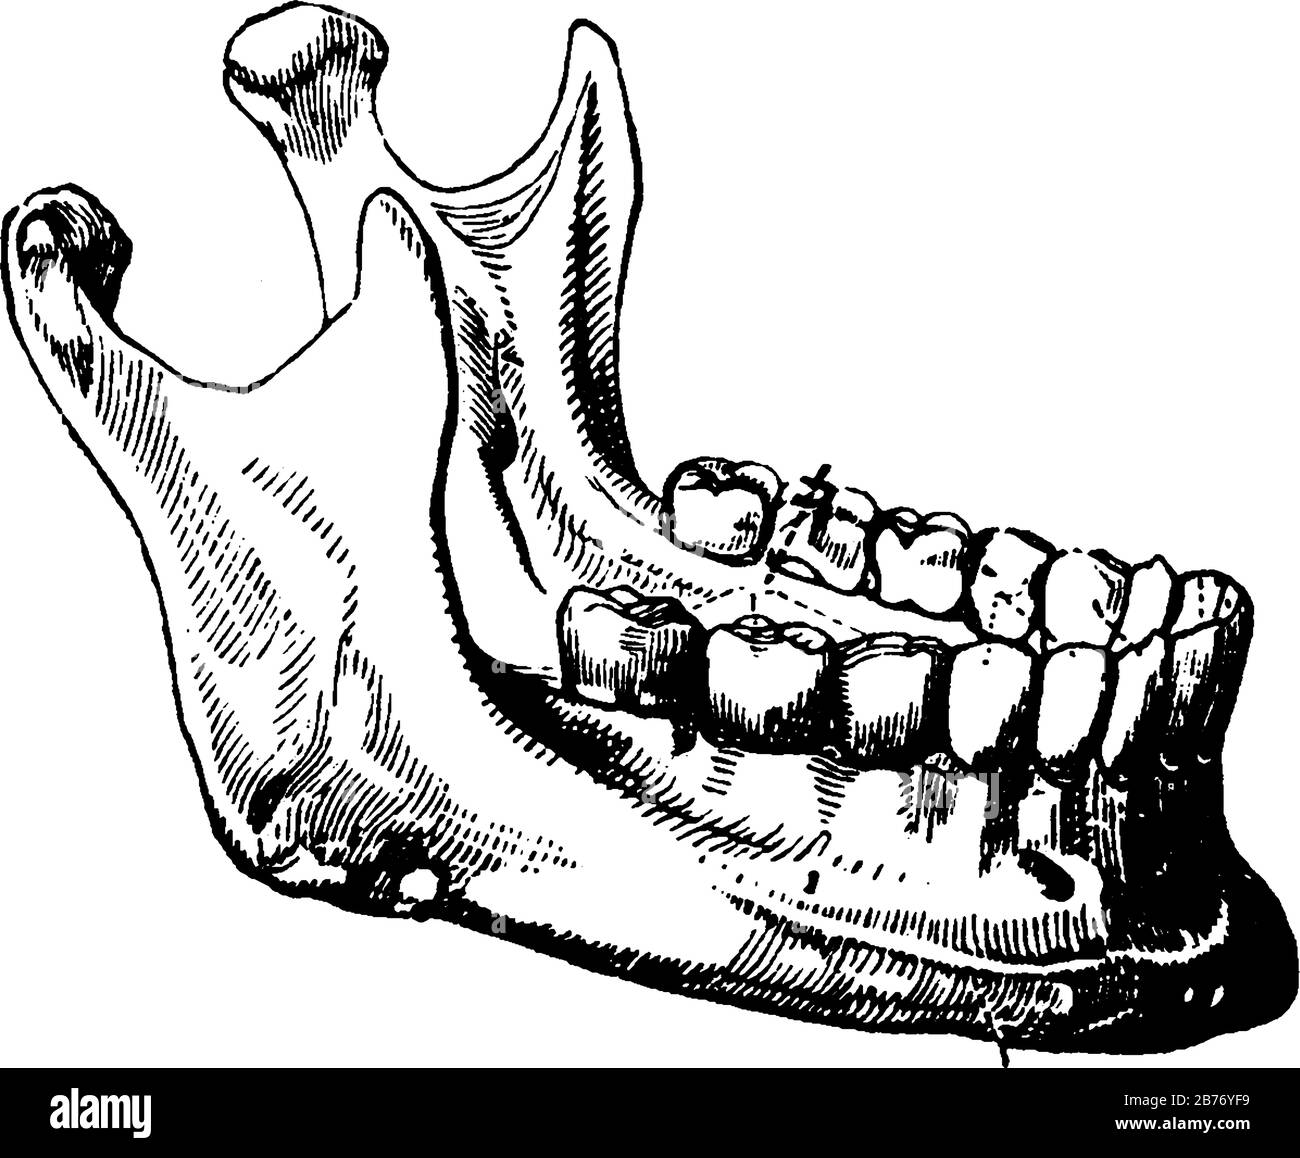

Le terme mandibulaire est donné aux dents de la mâchoire inférieure. La bouche adulte a 32 dents, l'intermédiaire quatre dents sur les mâchoires inférieures, dessin vintage Illustration de Vecteurhttps://www.alamyimages.fr/image-license-details/?v=1https://www.alamyimages.fr/le-terme-mandibulaire-est-donne-aux-dents-de-la-machoire-inferieure-la-bouche-adulte-a-32-dents-l-intermediaire-quatre-dents-sur-les-machoires-inferieures-dessin-vintage-image348663261.html

Le terme mandibulaire est donné aux dents de la mâchoire inférieure. La bouche adulte a 32 dents, l'intermédiaire quatre dents sur les mâchoires inférieures, dessin vintage Illustration de Vecteurhttps://www.alamyimages.fr/image-license-details/?v=1https://www.alamyimages.fr/le-terme-mandibulaire-est-donne-aux-dents-de-la-machoire-inferieure-la-bouche-adulte-a-32-dents-l-intermediaire-quatre-dents-sur-les-machoires-inferieures-dessin-vintage-image348663261.htmlRF2B76YF9–Le terme mandibulaire est donné aux dents de la mâchoire inférieure. La bouche adulte a 32 dents, l'intermédiaire quatre dents sur les mâchoires inférieures, dessin vintage